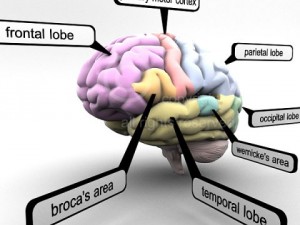

A blend model of brain along with its covering layers (meninges), skull bone and scalp labelled in detail and anatomically precise. The parts depicted are white, gray, pia, arachnoid, dura, bone, skin, fat, aponeurosis, periosteum, falx cerebri and more.